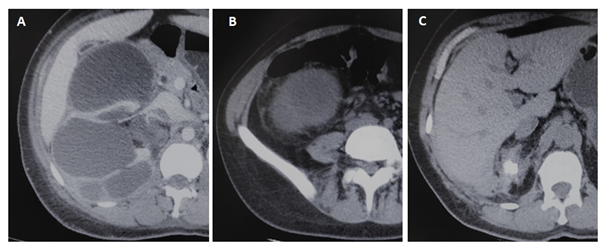

Eighty four patients with a poor functioning kidney associated to pain or severe infection were submitted to nephrectomy in our Institution (Table 1). The main tomographic findings were hydronephrosis (71.4%), fat stranding (63%) and adherence to liver/spleen (29.6%) (Figure 1).

Figure 1 Preoperative tomographic findings in patients submitted to laparoscopic nephrectomy for urolithiasis: (A) Hydonephrosys, (B) Fat stranding, (C) Adherence to liver.

Preoperative enhanced CT scan plays an important role demonstrating calculi, hydronephrosis, determining the extension of the inflammatory process, evidencing abscesses, fistulae (renocolic or cutaneous) and adherences to adjacent structures (psoas muscle, back or abdominal wall muscles, pancreas, liver and spleen) which predict an upcoming complex procedure (Figure 1). Herein we demonstrated the key importance of tomographic features in predicting conversion to open nephrectomy. In univariate analysis, fat stranding, renal, perirenal and pararenal abscess, fistula and adherences to adjacent structures were significantly more frequent in the conversion group. Multivariate analysis revealed that pararenal abscess and adherence to the bowel were significant risk factors for conversion to open procedure. All patients who presented a pararenal abscess on preoperative tomography had their procedures converted to open access, which gives this parameter statistical significance even with a reduced number (n=3).